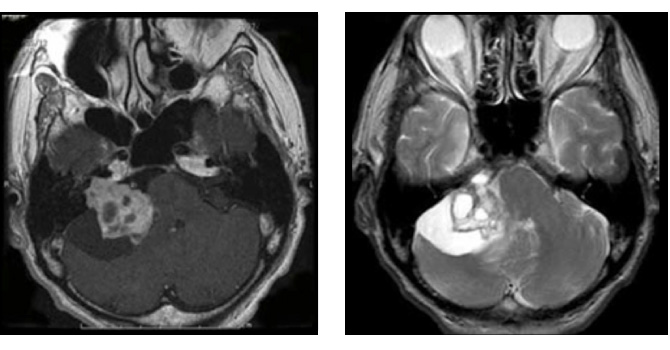

図3はガンマナイフ後、残念ながら増大してしまった50代男性の腫瘍です。聴覚はすでに失われておりましたので、注意深く顔面神経を保護しつつ手術を行い、95%摘出しました。術後問題なく社会復帰されています。

図3:50代男性 ガンマナイフ後3年半で拡大

(左図)ガンマナイフ時(中図)3年半後(右図)手術後 術後4年経過するも再増大なし

図4:神経繊維腫症2型の症例

42歳女性 両側の聴神経腫瘍をみとめる。NF2の症例。両側とも聴覚は良好であり、大きい方の腫瘍をまず摘出。聴覚は術後やや低下したが温存された。右の小型聴神経腫瘍は拡大傾向なく経過を観察している。

▲ 術前MRI

▲ 術後MRI 左側の腫瘍は被膜を残して摘出されている

▲ 術後左聴覚は25dBまで低下したが、良好な温存。